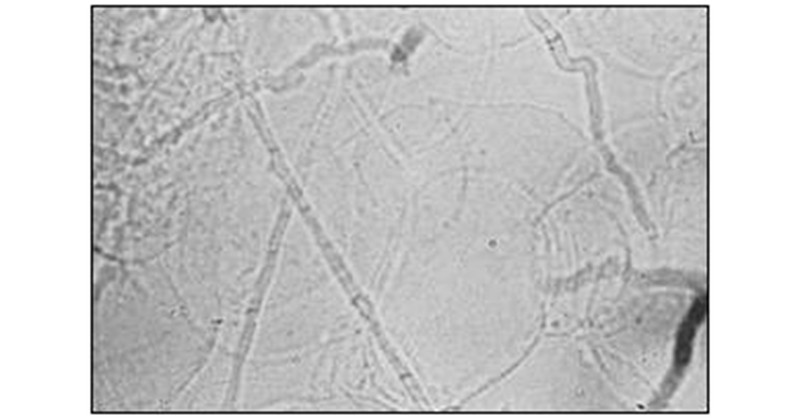

The procedure involves obtaining skin scrapings from the active border of a lesion using a scalpel blade or a glass slide. The scales are the transferred onto a glass slide, wherein a few drops of KOH 10% are added and the preparation is allowed to stand for 15 to 30 minutes to allow the keratin to dissolve. The well-mounted preparation is then examined under a microscope (40X) which allows visualisation of the fungal hyphae which appear as branching, rod-shaped filaments of uniform width with septa (figure 1).

Fig.1: Fungal hyphae

A modification to this method is the use of Chicago Sky-blue stain along with 10% KOH for better visualisation of the fungal hyphae. [2]